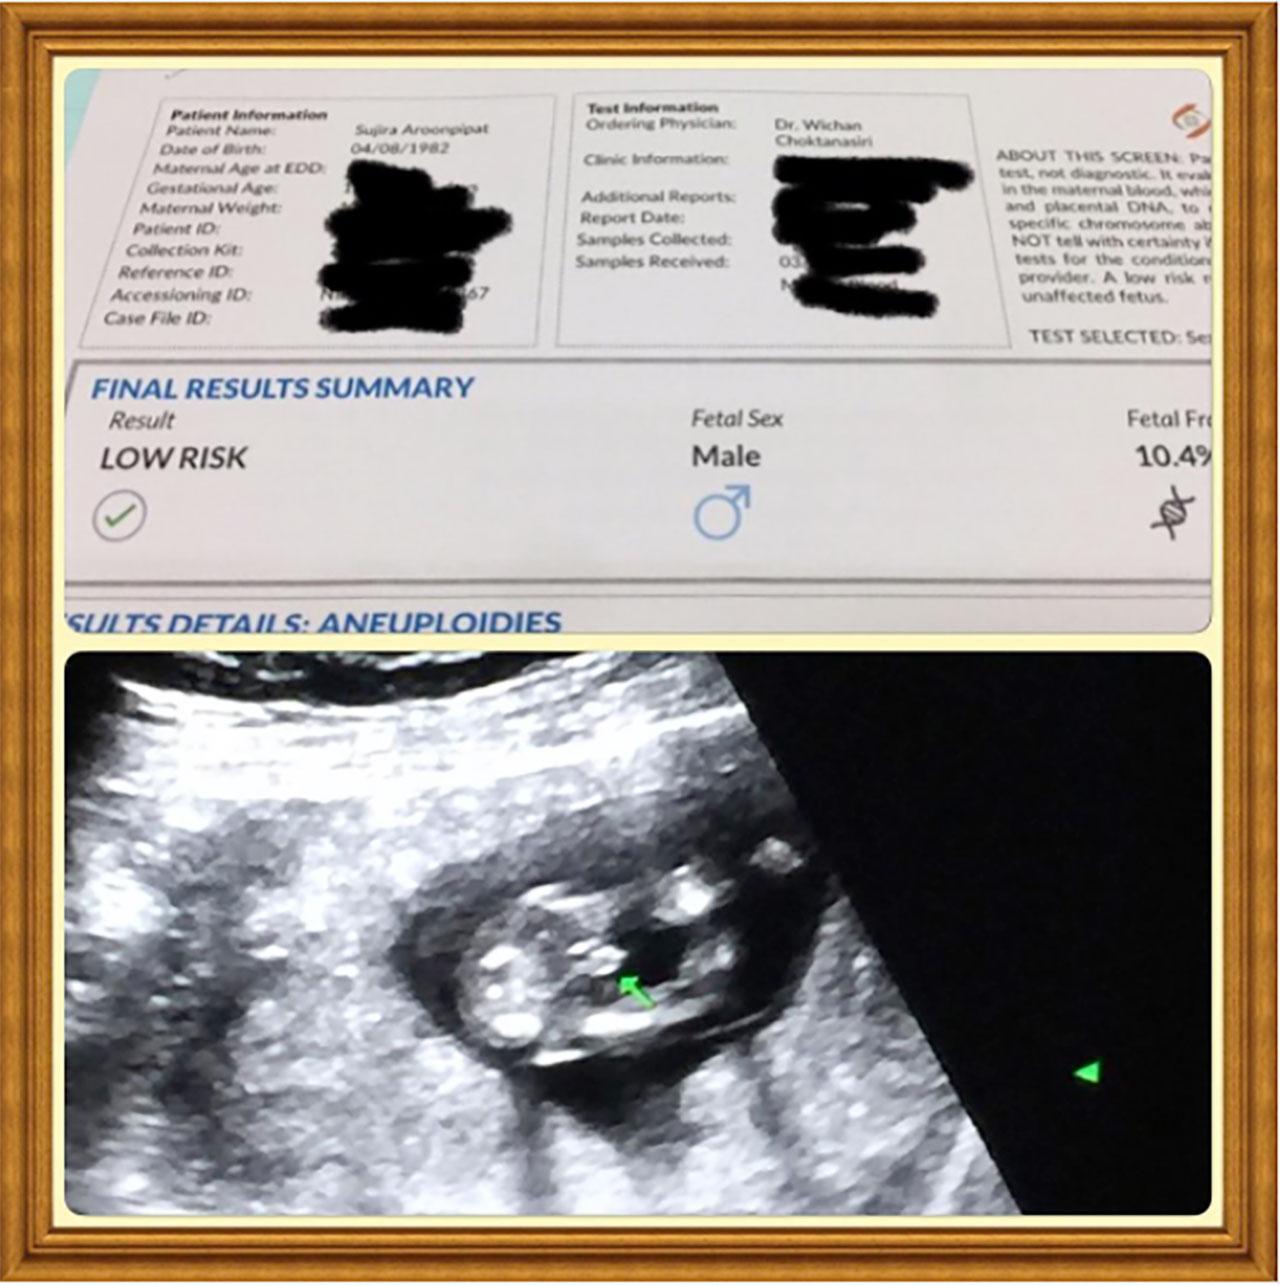

ตอนนี้เพิ่งเริ่มยังไม่มีอาการ แต่วันนี้ (5 เม.ย.) ไปตรวจและรู้ว่าได้ลูกผู้ชาย น้องแข็งแรงดี อายุครรภ์ 3 เดือน กำลังจะเข้าเดือนที่ 4 ค่ะ และตอนนี้น้องรดารู้แล้ว แต่ยังไม่รู้ว่าเป็นน้องผู้ชาย เราต้องเตรียมให้คนพี่เข้าใจก่อนว่าจะมีเบบี๋ ซึ่งคุณหมอก็บอกว่า ให้พ่อแม่ให้ข้อมูลกับลูกคนแรกก่อนว่า น้องคือของขวัญของเรานะ พอโตขึ้นเราจะได้ดูแลกันนะลูก

พร้อมเผยว่าพอมีน้องคนที่สองก็จะปิดอู่เลย เพราะไม่ไหวแล้ว อยากจะเลี้ยงลูกสองคนให้เป็นคนที่มีคุณภาพ เราจะได้ดูแลทั่วถึง รู้สึกโชคดีที่วันนี้ไปตรวจแล้วรู้ว่าเป็นน้องผู้ชาย เราคิดว่ามันครบแล้ว มีลูกสาวและลูกชาย แต่อนาคตไม่แน่ถ้าติดใจอาจจะมีอีกคนที่สามก็ได้ ก็เลยคิดว่ายังไม่ทำหมัน แต่ปิดอู่ไปก่อน ตอนนี้เราต้องรื้อวิชาการเลี้ยงเบบี๋ขึ้นมาใหม่หมด

ทางพี่ปอนด์ พอเค้ารู้เค้าดีใจมาก เห่อมาก ลงรูปก่อนนุ้ยอีก ในความจริงจะได้ลูกผู้หญิงหรือผู้ชายก็ได้ เหมือนกัน แต่พอรู้ว่าได้ลูกผู้ชาย รู้สึกเหมือนโชคดี 2 เด้งเลย ครบแล้ว หญิง 1 ชาย 1 ปิดอู่ได้ (หัวเราะ)